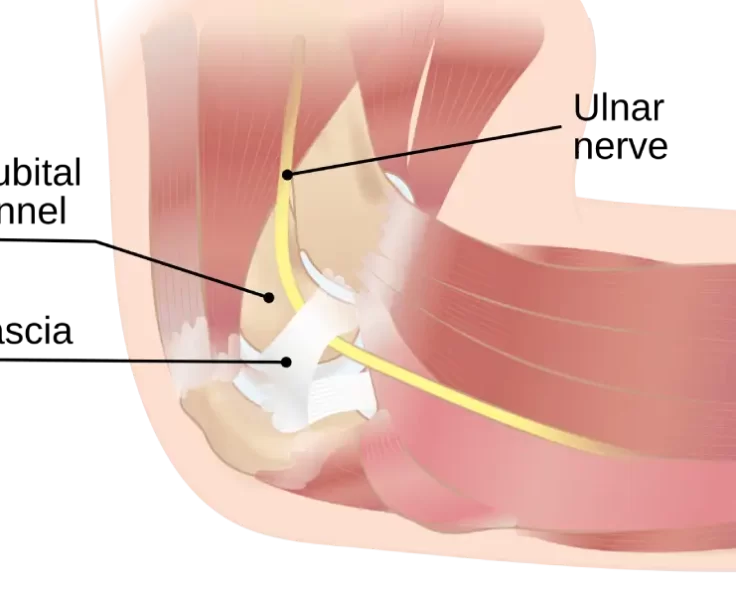

Ulnar Nerve Release

The ulnar nerve is one of the three main nerves in the arm that runs from the neck to the little finger, passing through a…